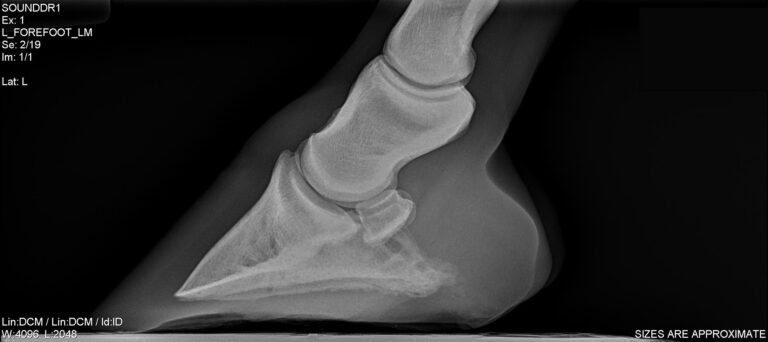

Tips and Tricks to Acquiring Great Equine Foot Radiographs

Hoof-rad-courtesy-Dr